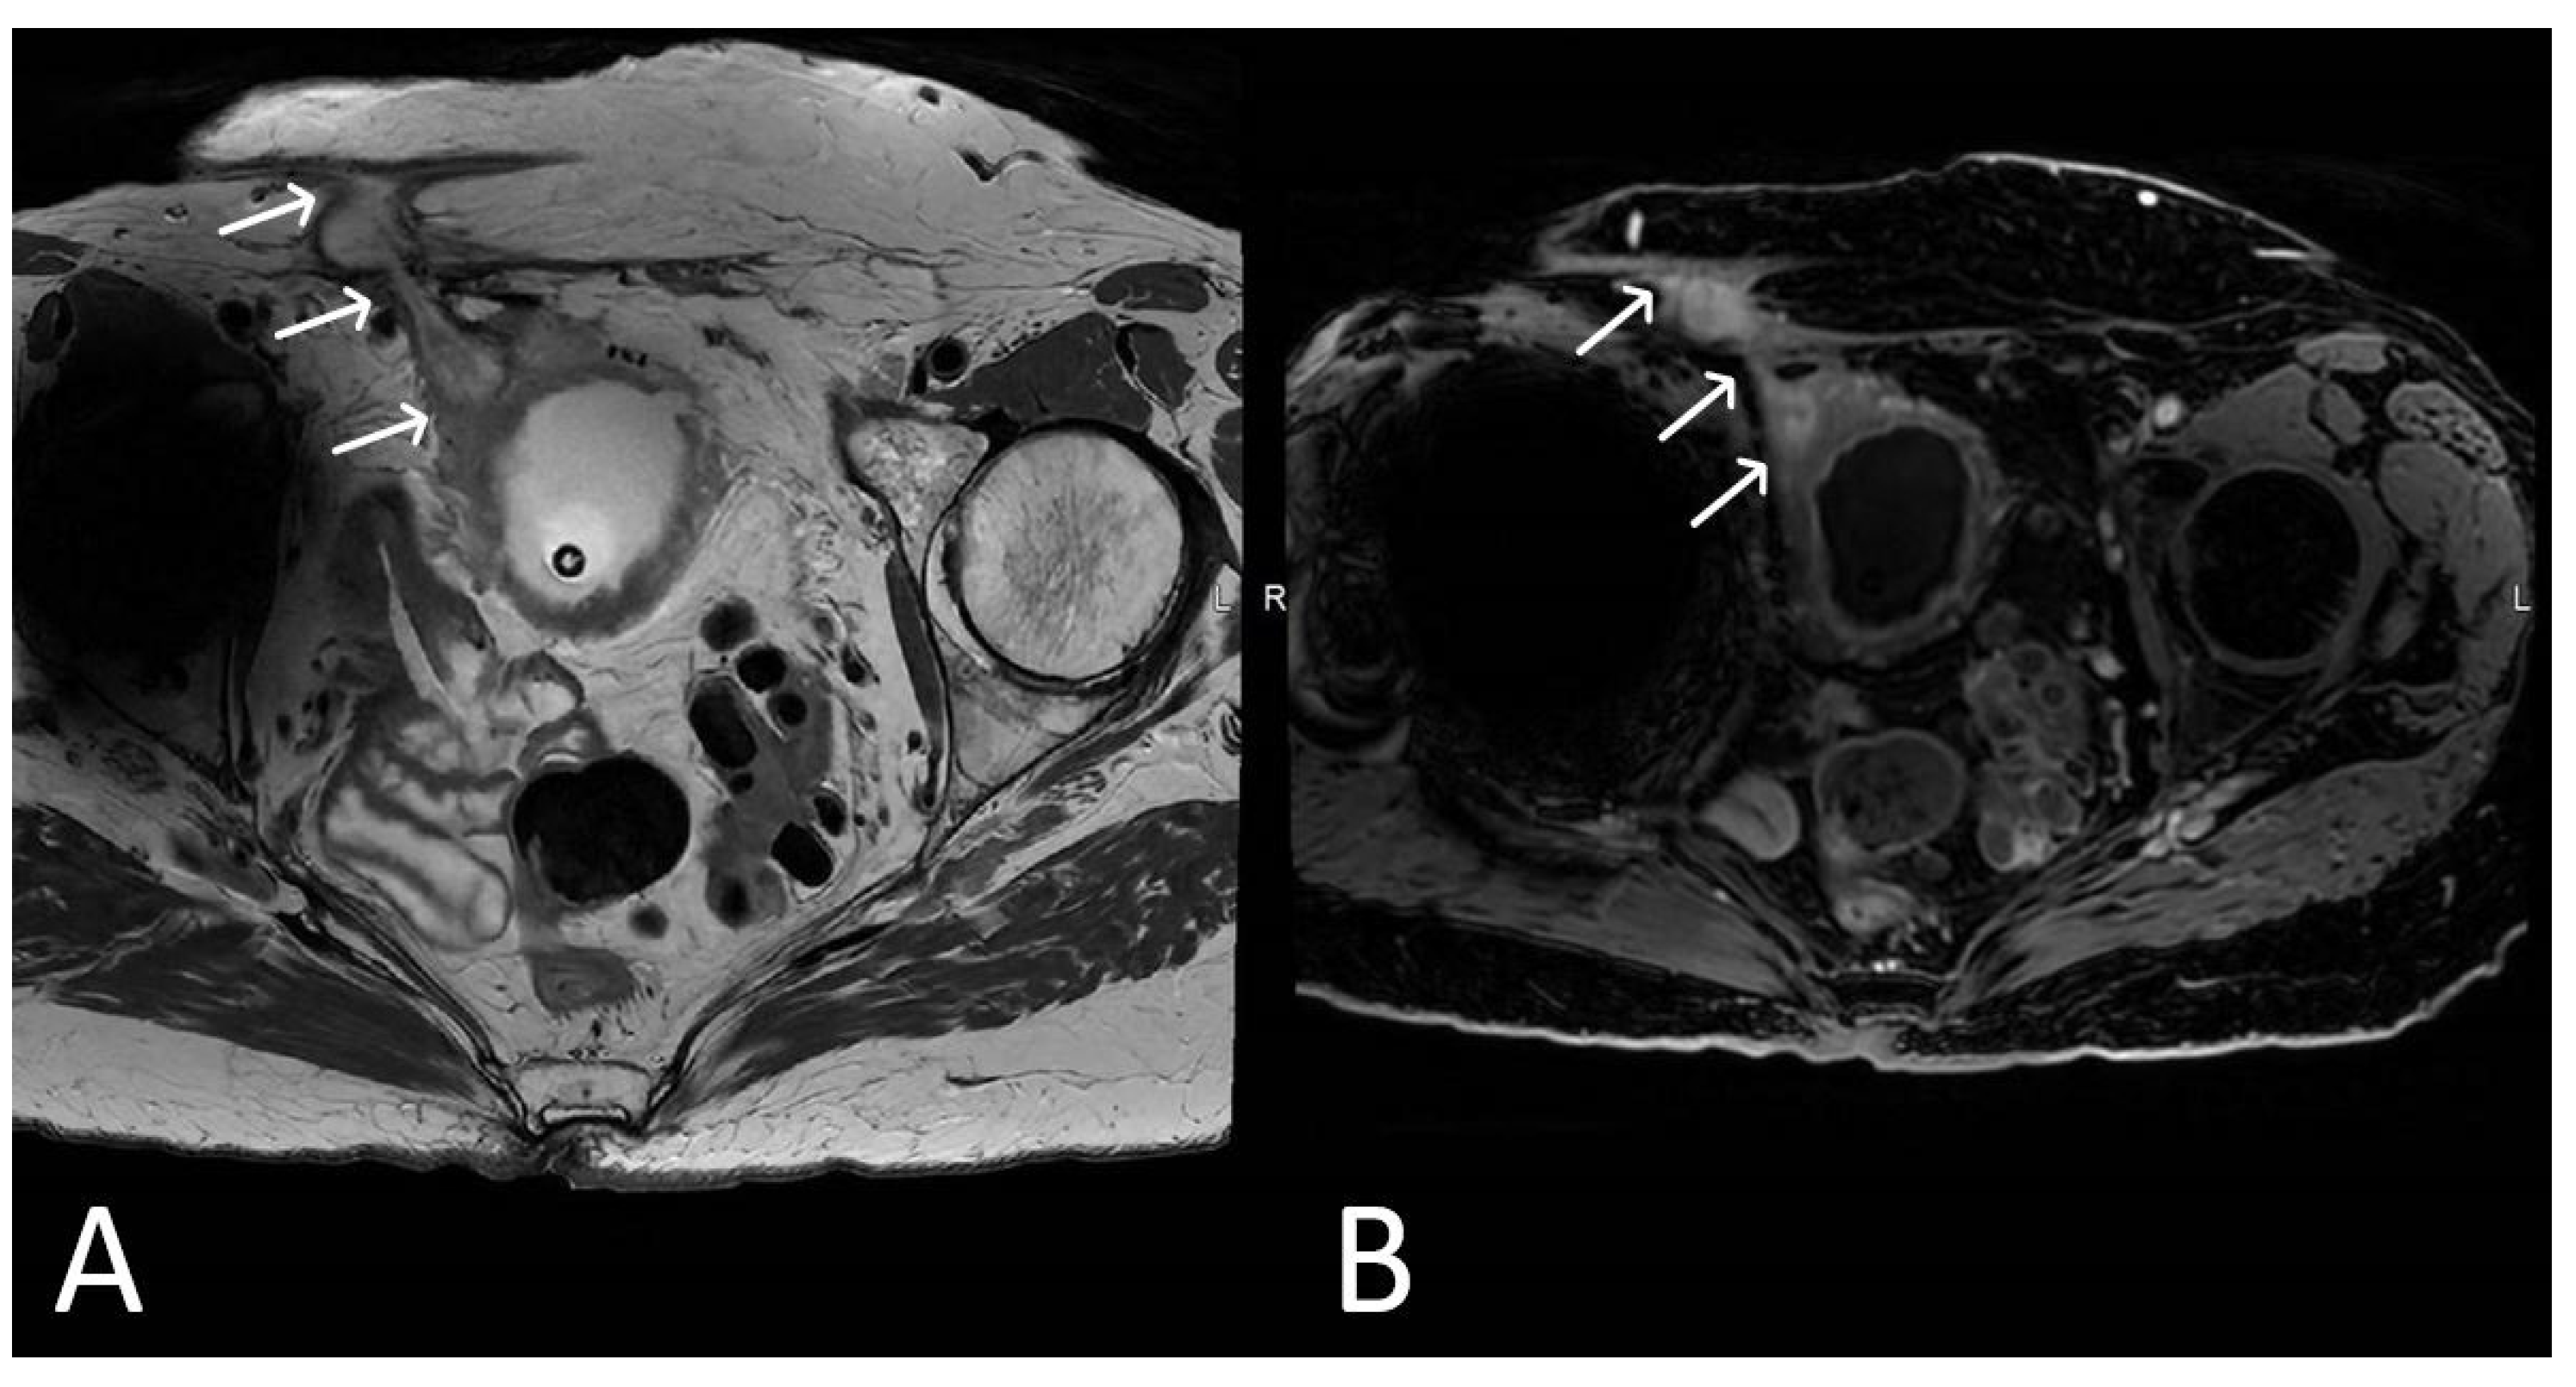

3. Normal Appearance of Urethral Meshes on MRI/CT

4. Urethral Mesh in Oncological Patients

5. Urethral Mesh Complications